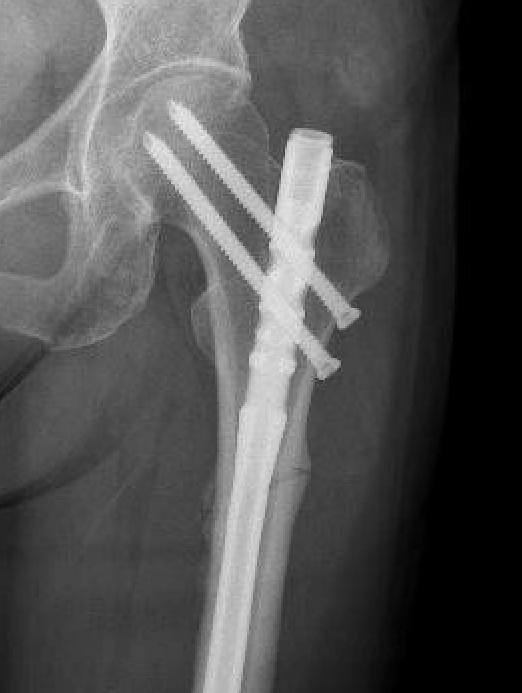

1. Cephalomedullary nail

- be careful of bowed femurs in Asian women

2.  Lateral plate and screws

- high failure rate

- consider in setting of severe bowing

Nail aptypical 1Nail atypical 2

Femoral stress fractureFemoral Stress Fracture IMN

complete AFFNail AFF